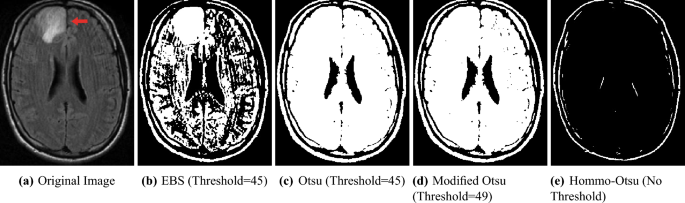

Brain tumor segmentation

Medical image analysis techniques using brain X-ray are used for early diagnosis and treatment planning, assisting radiologists in identifying and evaluating brain tumors. We acknowledge using this \(279\times 344\) original image from the Brain Tumor Dataset29. The contents of this dataset are licensed under DbCL v1.0 (https://opendatacommons.org/licenses/dbcl/1-0/). It shows the brain X-ray of a tumor patient, with the tumor’s location indicated by the red arrow. As shown in Fig. 8, the EBS method effectively highlights the tumor contour, though some white noise is still present in surrounding areas. In contrast, other methods struggle to segment the tumor, focusing mainly on the overall brain contour.